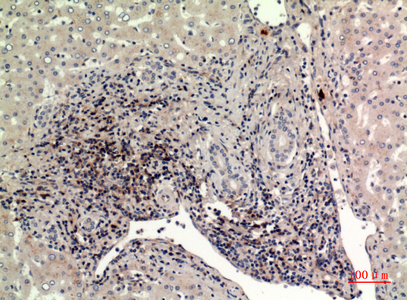

WB,IHC-P,IF-P,IF-F,ICC/IF,ELISA

WB 1:500-1:2000, IHC-P 1:100-1:300, ELISA 1:20000, IF-P/IF-F/ICC/IF 1:50-200